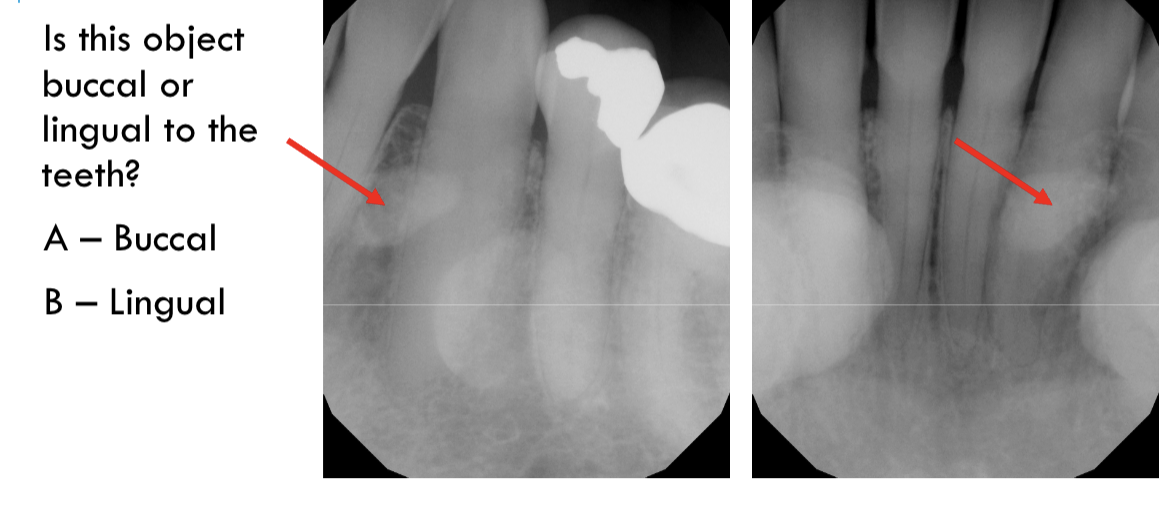

buccal object rule

expose 1st image (PA or bw)

take a second image with a different H or V angulation aka same area different angle

compare images to see how the object shifted in the image

SLOB

buccal

lingual

unable to assess from this single image the objects buccal-lingual position relative to the teeth